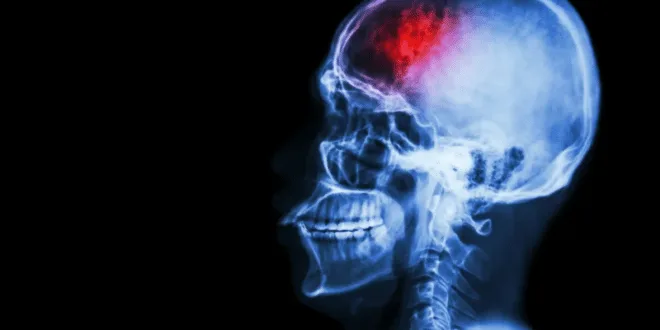

Se ti fanno spesso male la spalla destra e quella sinistra, ecco a quale organo hai effettivamente problemi:

Reagisci in tempo: se hai dolore alla spalla, potrebbe trattarsi di problemi a uno degli organi più importanti del corpo! L’articolazione della spalla è una delle più mobili, ma anche una delle più instabili del corpo. È quella che usiamo di più ogni giorno in attività come: pettinarci, vestirci, mangiare, fare esercizio fisico, guidare…